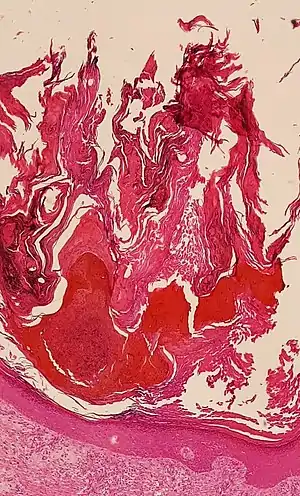

![]() Histologic image of human epidermis in thick skin | |